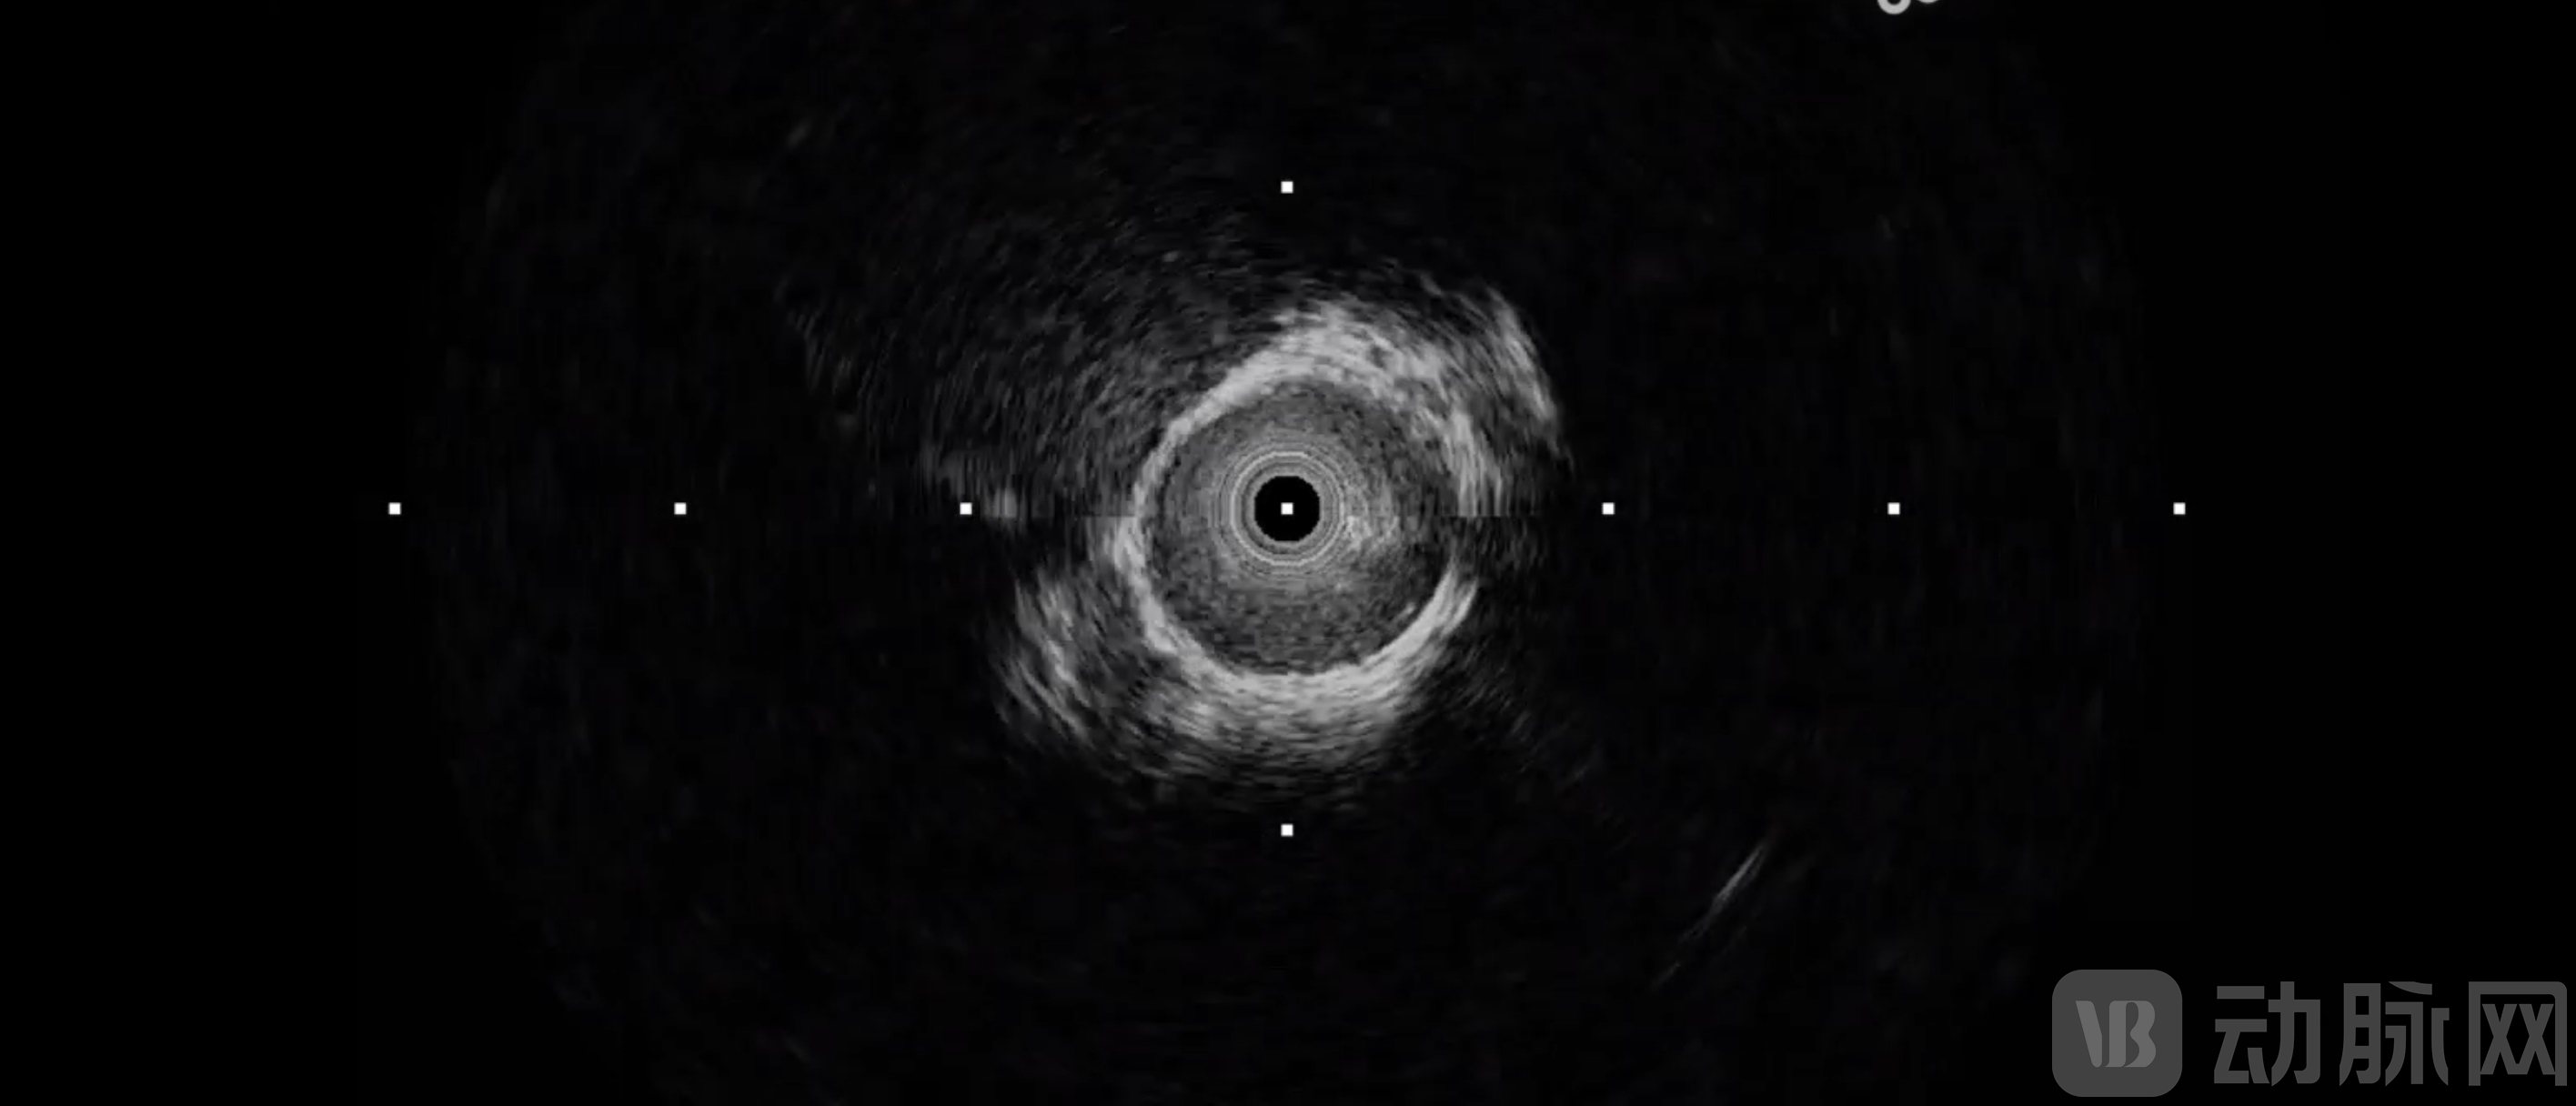

图为Neuro-IVUS脑血管成像图像

综上,Neuro-IVUS实现了脑血管介入的高频超声成像,让医生从“凭经验盲操”转向“可视化精准治疗”。其临床价值贯穿诊疗全程:术前精准识别易损斑块,科学规划器械选型;术中即时发现支架贴壁不良、血管夹层等急性并发症并立即补救;术后即刻验证疗效,实现“植入即评估”的闭环管理。推动脑血管介入从“经验医学”迈向“精准医学”。